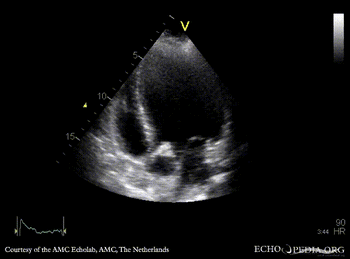

Endocarditis of aortic valve

PLAX: vegetations on aortic valve PSAX: thickend bicuspid aortic valve